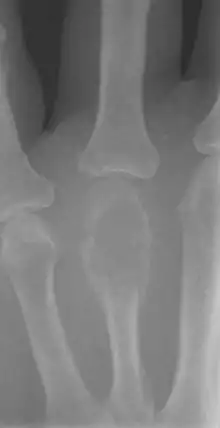

On X-ray, giant-cell tumors (GCTs) are lytic/lucent lesions that have an epiphyseal location and grow to the articular surface of the involved bone.[8] Radiologically the tumors may show characteristic 'soap bubble' appearance.[9] They are distinguishable from other bony tumors in that GCTs usually have a nonsclerotic and sharply defined border. About 5% of giant-cell tumors metastasize, usually to a lung, which may be benign metastasis,[10]

Plain radiograph is still the main method of diagnosing giant cell tumour. But MRI and CT scans are useful for staging and surgical planning. CT is more superior than plain radiograph in delineating the tumour outline, its extension into structures outside the bone, determining the involvement of bony cortex and tumour recurrence. CT scans show features such as thin and expanded bony cortex, with or without bony matrix calcifications, and fluid levels due to aneurysmal bone cyst or bleeding within tumour. However, axial views of the subarticular bone (bony area adjacent to the articular cartilage) is not accurate due to voxel signal averaging. MRI is superior than CT on delineating the tumour because of its better contrast resolution and imaging in multiple planes. MRI is also useful in determining the extension outside the bone and evaluating the involvement articular surface, skip lesions within bony matrix, and medullary cavity. However, bony cortex destruction is better demonstrated on CT scan.[11]

On MRI, the mass generates intermediate to reduced signal intensity on T1-weighted images, and increased signal intensity on fluid sensitive MRI images such as short tau inversion recovery (STIR). The mass enhances after intravenous gadolinium administration.[11]